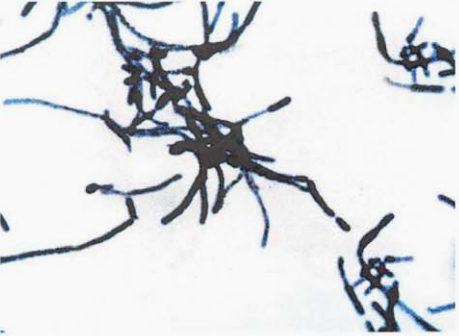

革兰阳性杆菌,在丝状的末端与一根短杆相连,形似“鞭子柄”状(图 4)。

图 4 马氏棒杆菌纯培养镜下形态(革兰染色)

在血琼脂平板上35℃培养18~24 h,形成扁平、丝状、蜘蛛样小菌落。

本菌特征:革兰阳性杆菌形似“鞭子柄”,触酶、硝酸盐还原试验阳性,分解葡萄糖。

马氏棒杆菌是一种少见的条件致病菌,偶尔从人的呼吸道分离到。如发现有附着于较大杆菌的纤细细菌,则可断定其为马氏棒杆菌,因为这种菌在活体内也常形成特征性的“鞭子柄”形态。